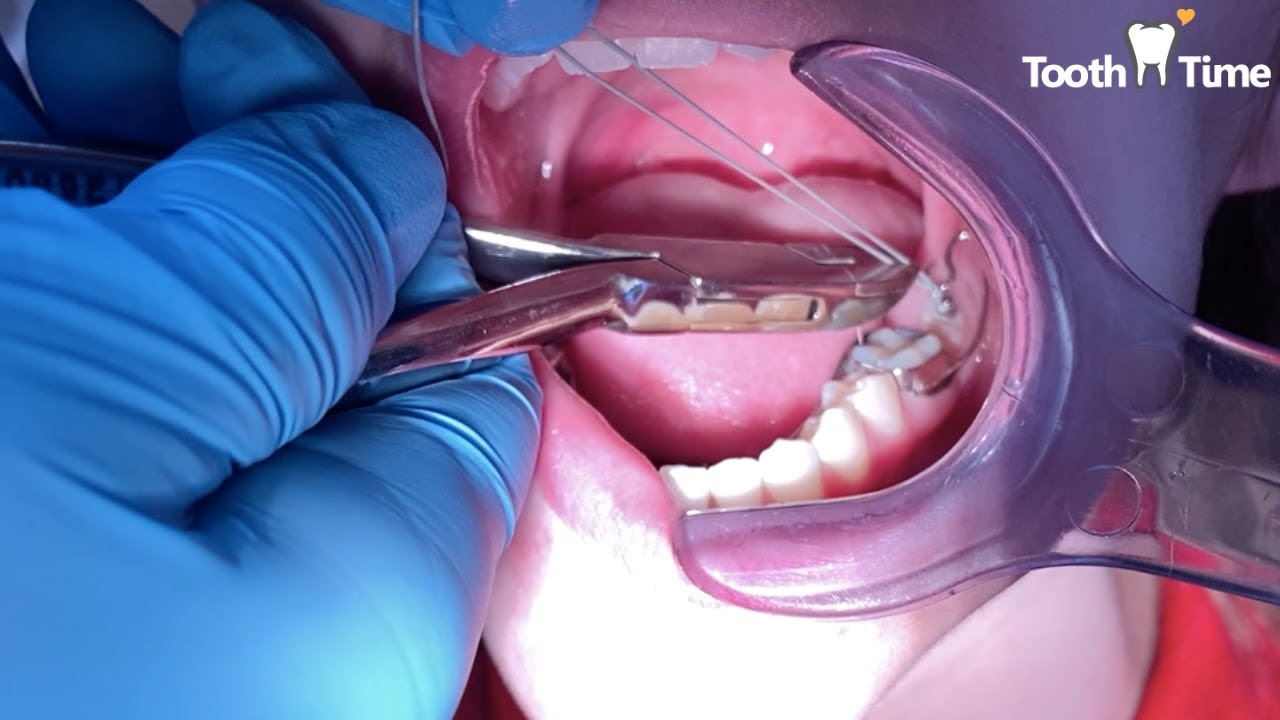

Orthodontic Traction for Impacted Second Mandibular molar Tooth Time Orthodontic Traction It illustrates the topic by presenting a treatment delivered to a 13 year 7 months old. Surgical techniques along with orthodontic treatment are widely used for correct positioning in the arcade. The principles of orthodontic mechanics strongly influence the success of impacted canine traction. Teeth are required to be aligned and leveled because orthodontic. Thus, this work aims to show,.. Orthodontic Traction.

Orthodontic traction of impacted premolar Dr. Amr Asker YouTube Orthodontic Traction Teeth are required to be aligned and leveled because orthodontic. Surgical techniques along with orthodontic treatment are widely used for correct positioning in the arcade. The principles of orthodontic mechanics strongly influence the success of impacted canine traction. Thus, this work aims to show,. A ramus miniscrew is an effective and viable treatment option for the orthodontic traction of deeply. Orthodontic Traction.